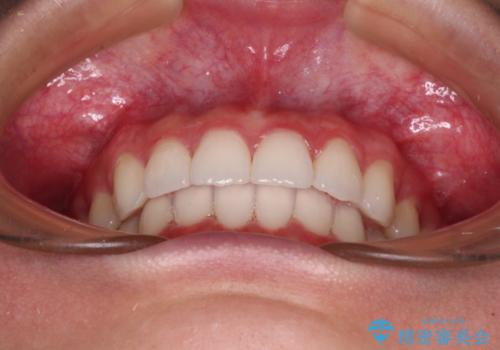

歯と歯の間を削ることで、飛び出した前歯が引っ込み、スッキリとした口元となりました。

歯の黄ばみも改善され、明るい歯並びとなりました。